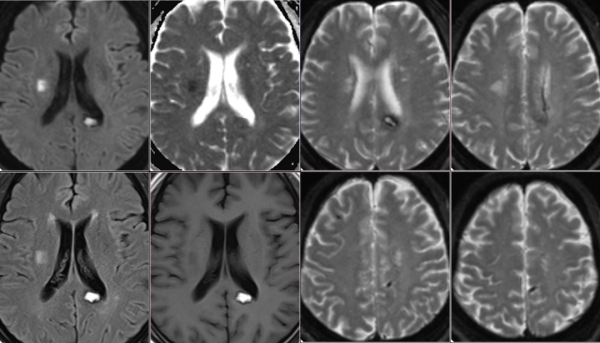

CT+MRI